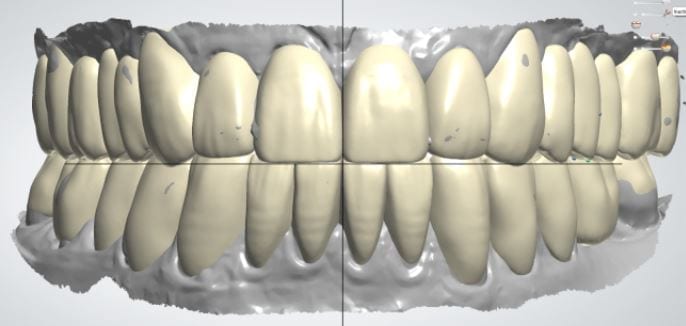

The digital models were then imported into a third party software where a library of tooth morphologies are available for the clinician to choose from.

Once the appropriate library is chosen, the digital wax ups are performed. In the subsequent photos you can see the transparent overlay of the wax-ups to the original position of the existing dentition

Once the case is designed to the ideal vertical dimension then multiple shells can be fabricated for treatment. The wax up model can be uniformly reduced by .5mmm’s circumferentially and a temporary shell can be designed. Once the teeth are prepared, these shells can be relined and seated onto the preps.